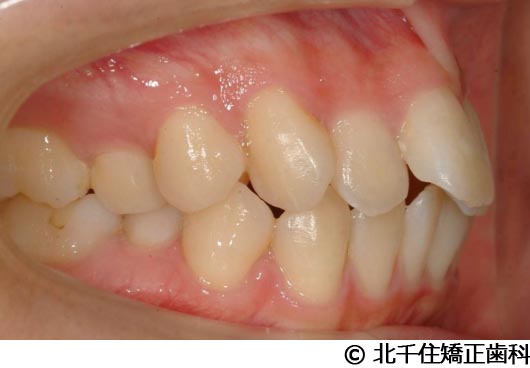

【症例5】上顎前突

- 治療前

- 治療後

- 治療名

- 上顎前突

- 費用

- 1,263,600円(税込)

- 期間

- 2年8ヵ月

- 治療回数

- 32回

- 通院頻度

- 1ヵ月ごと

- 年齢

- 13歳3ヵ月(初診時)

治療内容

-

患者様の症状

主訴:出っ歯

治療方法

骨格性の上顎前突、ヘッドギアを併用して上下顎第一小臼歯4本抜歯してワイヤー矯正。

治療結果

骨格性上顎前突に対し、ヘッドギアおよび抜歯を併用した矯正治療により歯列および咬合関係の調整を行った症例である。

治療後は保定装置を使用し、歯列および咬合の安定維持を目的として定期的な経過観察を行っている。

※治療結果は個人差があります。

治療を行う上での注意点(リスク・副作用)

歯磨き不良に伴うカリエスや歯周病、歯根吸収など。